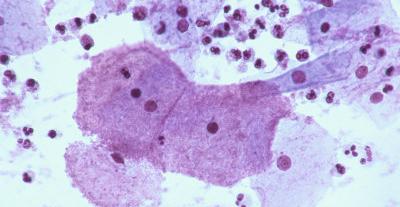

Контрольное проведение бактериоскопии назначается через неделю после завершения курса лечения, повторное — через 1-1,5 месяца.